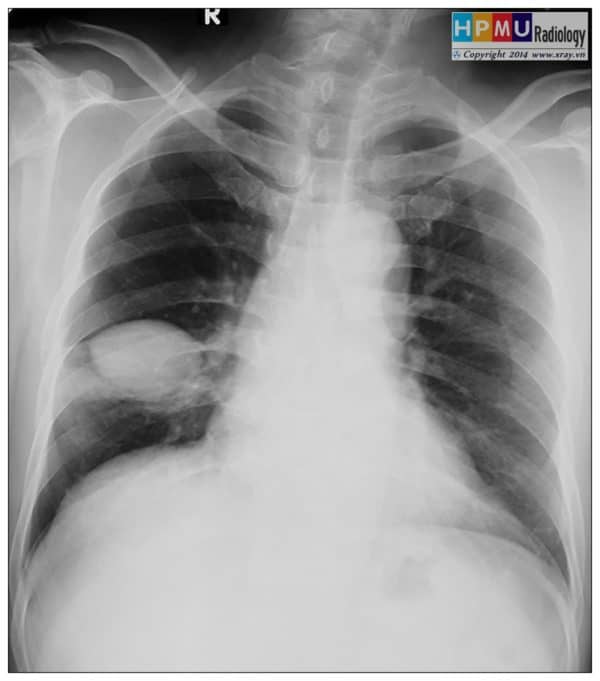

Tràn dịch màng phổi

Tràn dịch màng phổi - Ảnh 2

Tràn dịch màng phổi - Ảnh 3

» Thông tin: Nam giới – 46 tuổi.

» Lâm sàng: Ho + tức ngực.

# Tràn dịch rãnh liên thùy phụ phổi phải.